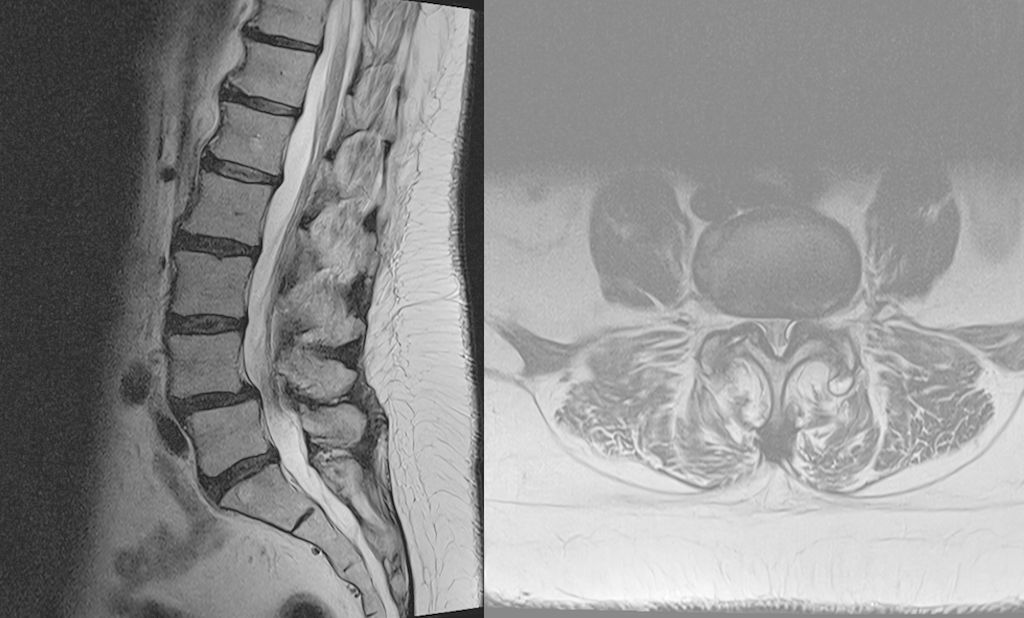

Fallbeispiel 1

Beispiel für die Implantation zervikaler Pedikelschrauben. In diesem Fall kam es bei einem 61-jährigen Patienten 10 Jahre nach anteriorer zervikaler Diskektomie und Fusion (ACDF) C4/5 und ventraler Verplattung C4–6 zu einer Ankylosierung auch von C6/7. Nach Sturz kam es zu einer Fraktur bei C6/7 mit begleitender Bogenfraktur und auch Beteiligung der dorsalen Ligamenta (Abb. 1 und 2). Klinisch bestanden ausgeprägte Nackenschmerzen und kein neurologisches Defizit. Es wurde die Indikation der dorsalen Verschraubung von C4 auf Th1 gestellt. Intraoperativ wurde routinemäßig zusätzlich eine kleine Referenzschraube in einer Lamina – entfernt von der Dornfortsatz-Referenzklemme für die Navigation – gesetzt. Mit dieser konnte intraoperativ die Genauigkeit der Navigation exakt überprüft werden (Abb. 4 und 5). Mittels navigierter High-Speed-Fräse wurden die Schraubenkanäle vorgebohrt (Abb. 6), im Anschluss wurde der Bohrkanal ausgetastet und die Schrauben wurden implantiert. Abbildung 7 zeigt eine Röntgenkontrolle 3 Monate postoperativ.